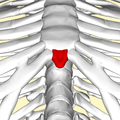

Posterior surface of sternum. (Xiphoid process labeled at bottom.) | |

Close up. Shape of a xiphoid process. Animation.

Shape of a xiphoid process. Animation.